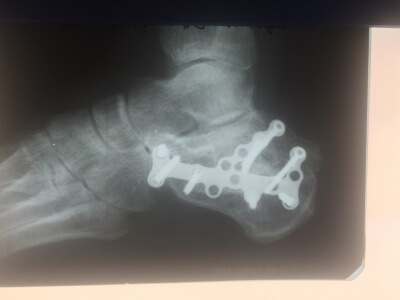

Применение материала Остеоматрикс при импрессионно-оскольчатом переломе пяточной кости